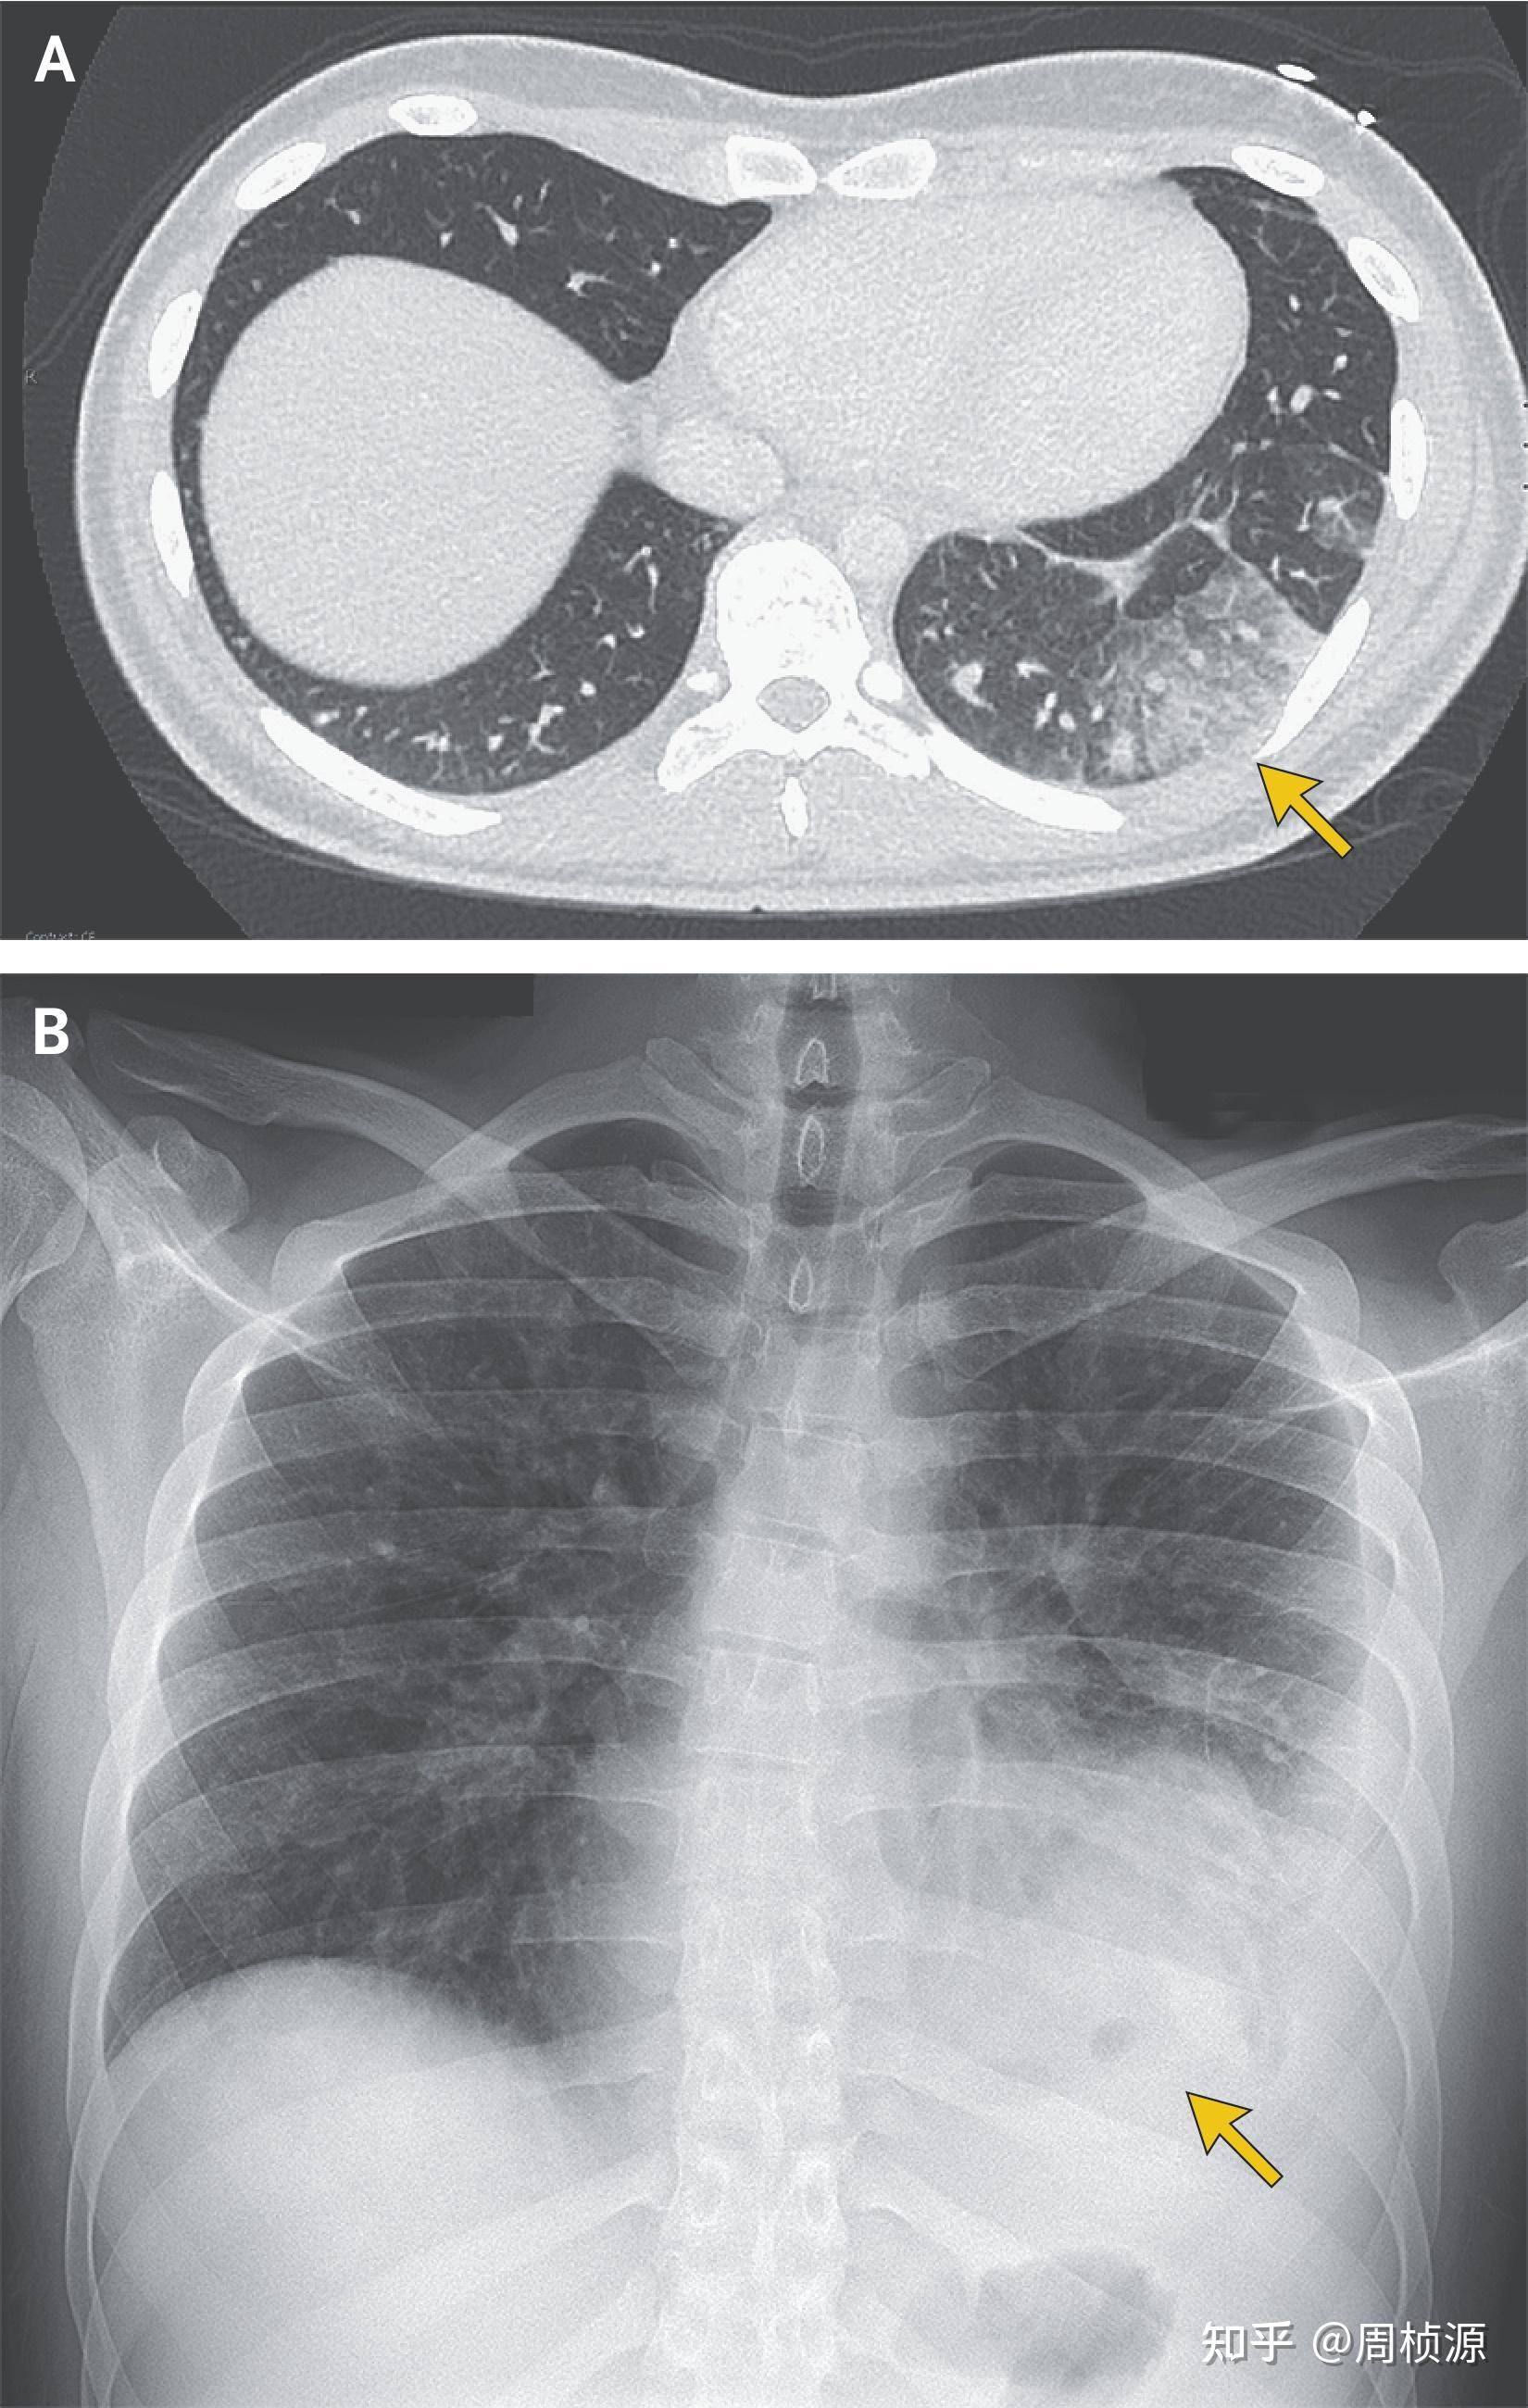

From zhuanlan.zhihu.com

Nejm 2021 Case 23 知乎 Nejm Case Report Impact Factor With a 2023 journal impact. the chart shows the evolution of the average number of times documents published in a journal in the past two, three and four years. journal impact factor nejm leads in the publication of influential, highly cited clinical research reports. journal citation reports offers data and analysis on journal performance and impact across. Nejm Case Report Impact Factor.